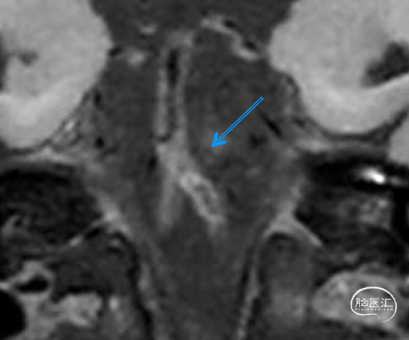

➢2024.07.10 MR:

核磁共振提示发病机制穿支事件+低灌注

高分辨核磁提示左侧椎动脉V4段不稳定斑块

患者高分辨核磁提示患者左椎动脉V4段-基底动脉闭塞,管壁不稳定斑块,开通过程中可能引起斑块脱落导致远端栓塞,因此手术重点需要兼顾远端血管保护及血管成型。应用COSIS技术,Syphonet®取栓支架保护远端正常基底动脉,同时还可以作为锚定装置,保留手术通道,减少器械交换次数,增加手术安全性。